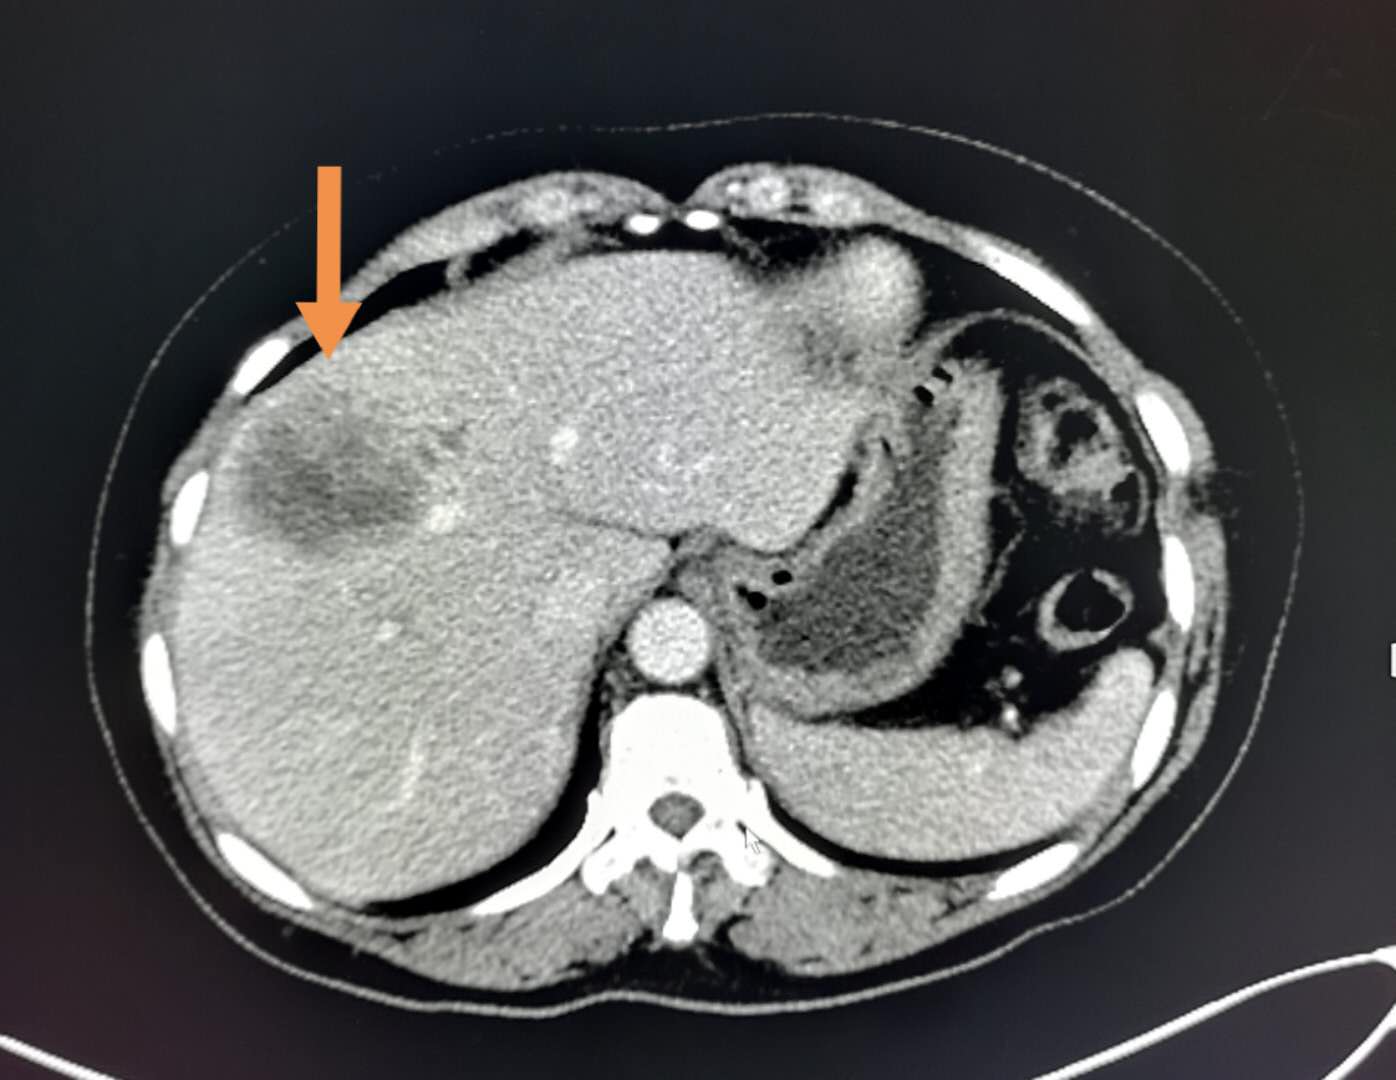

这绝对不正常,要查原因,最常见的就是胰腺和胆管肿瘤。

增强CT查出胆管癌,接近4厘米,无转移,有手术机会。